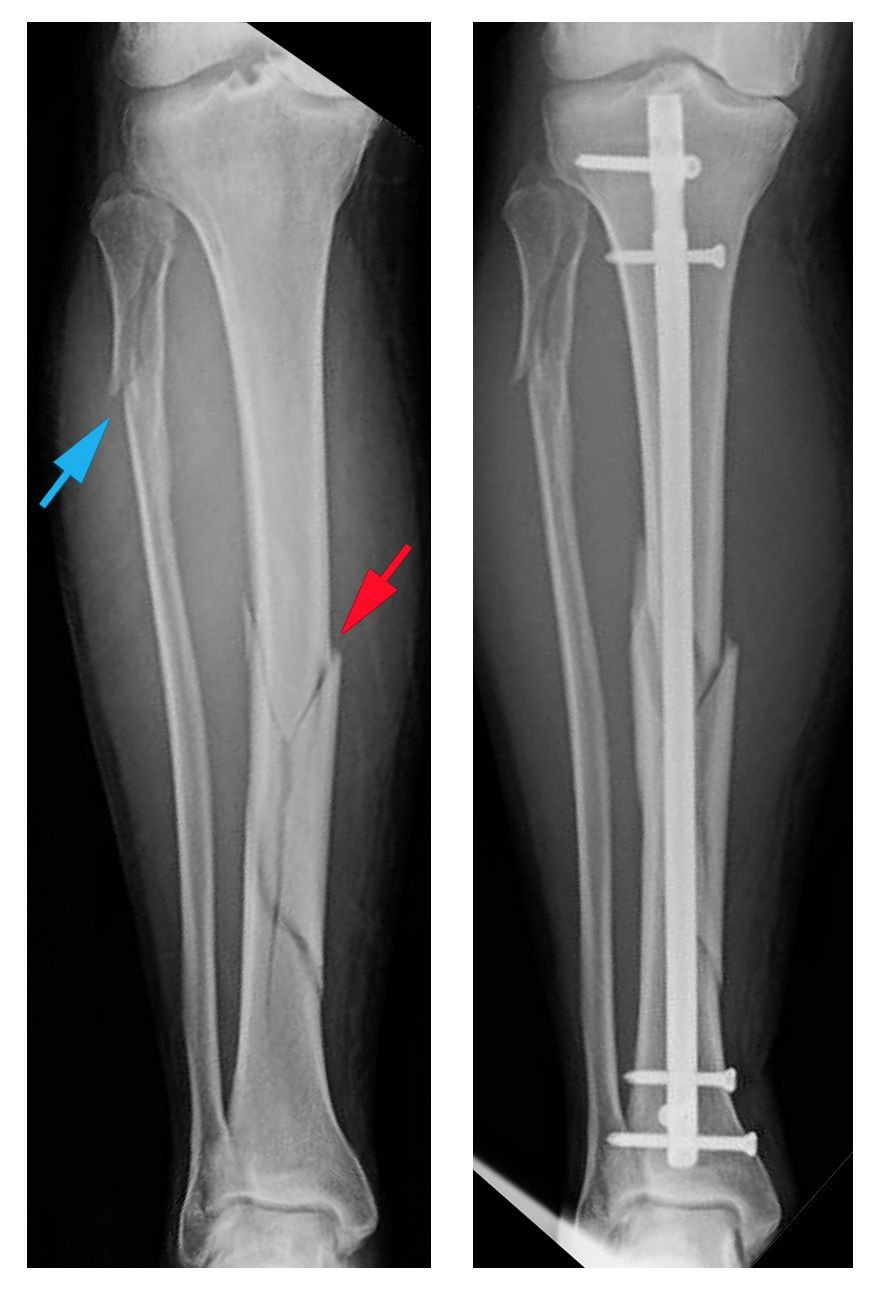

Tibia And Fibula Fracture Recovery Time

Tibial Nail Recovery Time Nail Ftempo